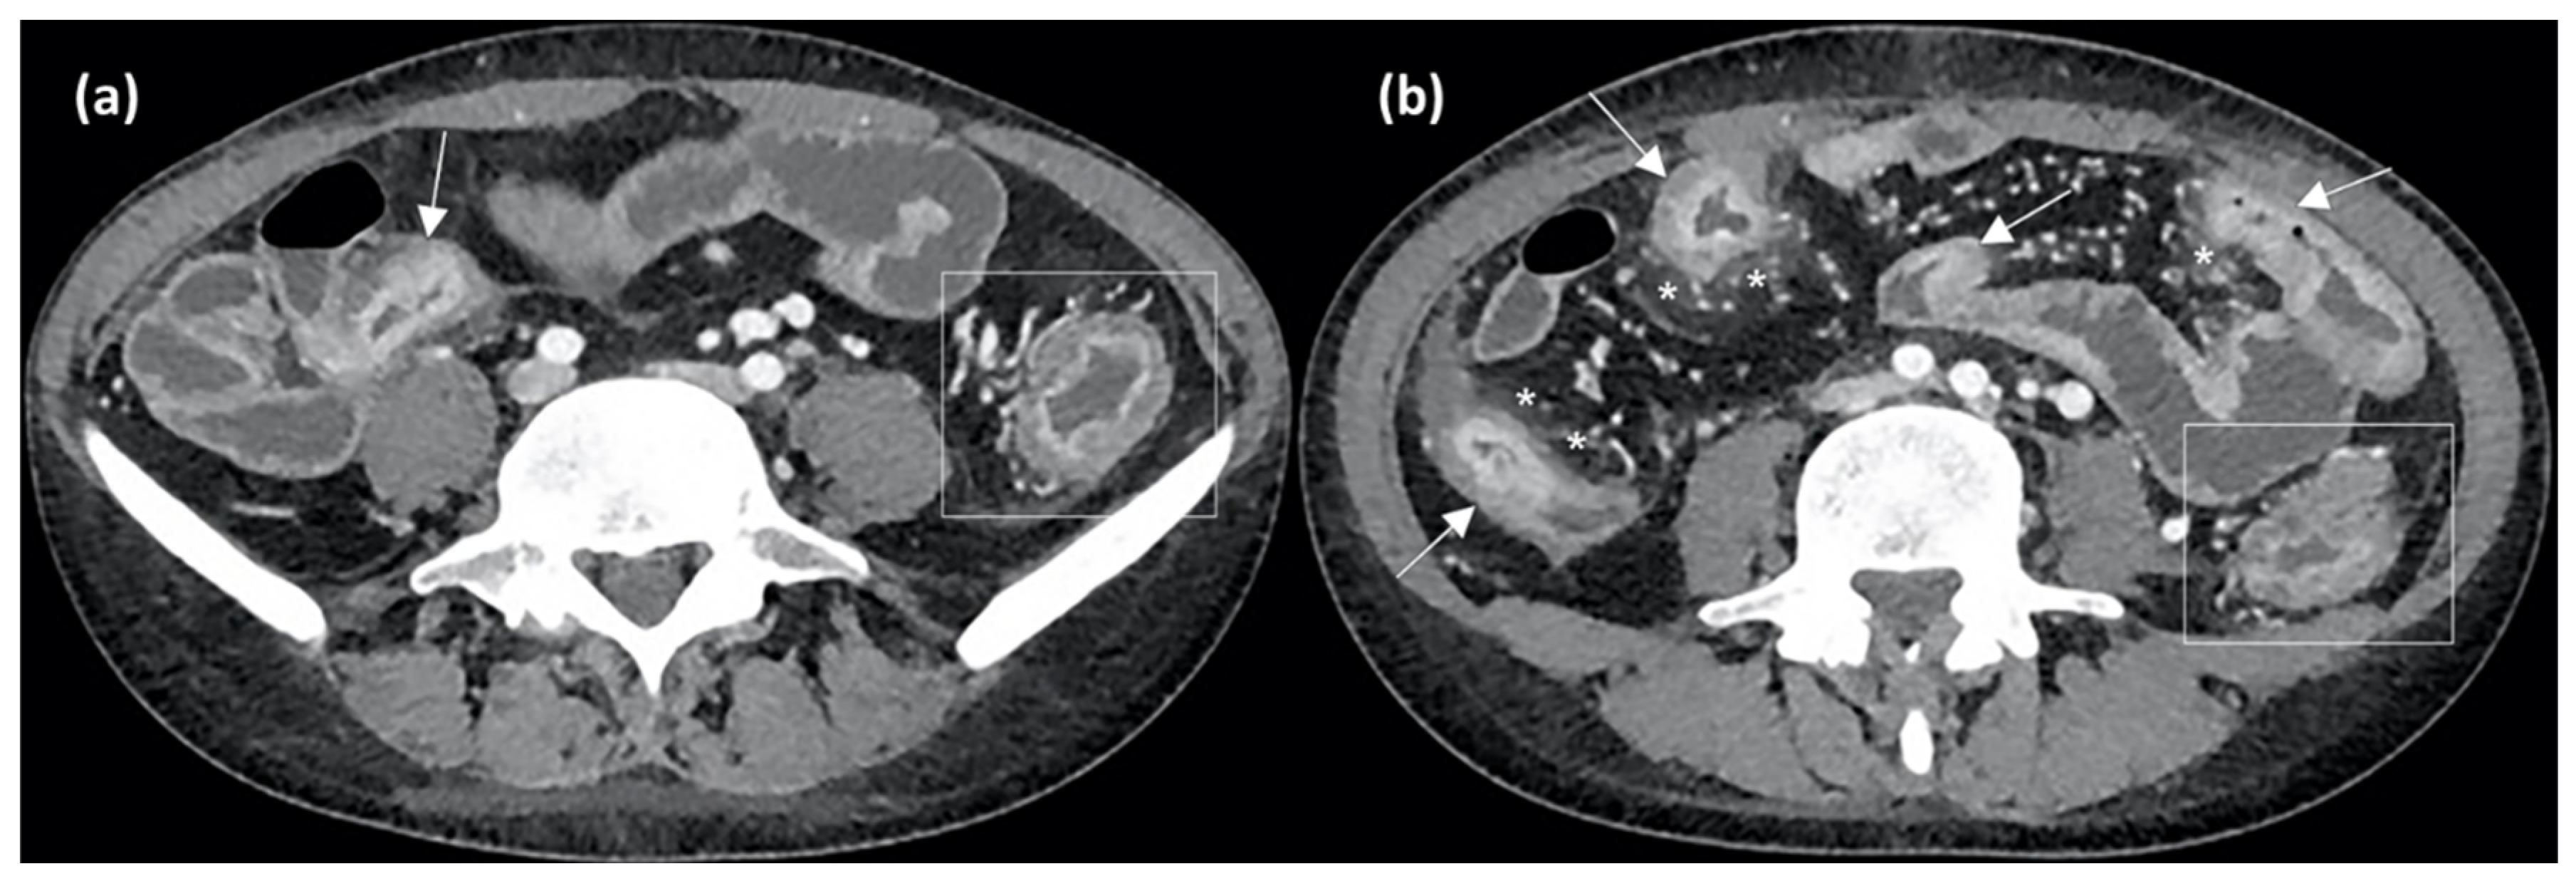

4. Computed Tomography Enterography and Radiomics

Similarly to MRE, TCE has a high accuracy in IBD diagnosis, being able to early detect mural inflammation, strictures, fistulas, and extra-enteric complications [75]. As for CD, it shows a specificity ranging from 90% to 100% for colon involvement and from 64% to 100% for small bowel lesions [76]. Increased BWT, increased wall contrast enhancement, and fat stranding are signs of active disease detectable with CTE as well as MRE, as shown in Figure 5.

Figure 5.

Axial CT enterography (CTE) images after contrast medium injection show wall thickening of the terminal ileum (arrow in (a)) and of other small bowel loops (arrows in (b)), with stratified contrast enhancement due to hyperdense aspects of the mucosal layer and hypodensity of the submucosal layer, indicating active inflammation. Perienteric fat stranding and local hypervascularization (asterisks in (b)) and left colonic wall thickening (rectangles in (a,b)) are also evident.